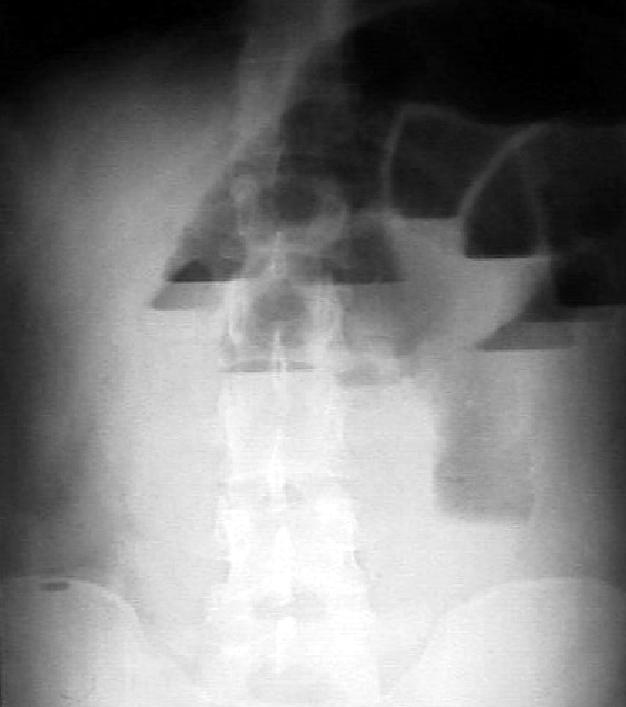

обеих сторон. На рентгенограмме подкова

двенадцатиперстной кишки несколько

развернута. На электрокардиограмме

отмечены косвенные признаки инфаркта

миокарда. Диастаза мочи – 512 ед. Произведено

ультразвуковое исследование поджелудочной

железы (см. рисунок).